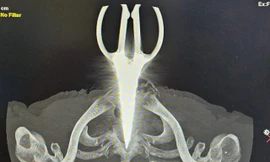

TPO - Các bác sĩ Bệnh viện Đa khoa Trung ương Cần Thơ thực hiện thành công ca can thiệp nội mạch nút túi phình mạch não kích thước lớn cho một bệnh nhân 90 tuổi - bệnh nhân cao tuổi nhất từng được can thiệp.